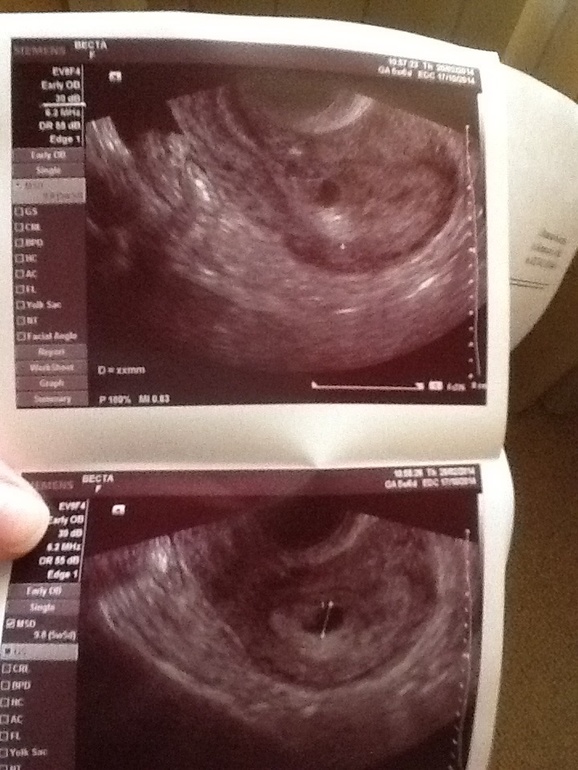

21 дпп ,сегодня пошла на узи. Врач смотрит и говорит:- я не вижу ПЯ!!! Что то есть,но нет желтого мешочка, удивляясь,ни чего не пойму.

Смотрела очень долго. Оказывается,мой пузожитель прикрепился у входа к матке на рубце от кесарева. Ели нашли ПЯ! Срок соответствует !

Но.....есть опасность пребывания беременности ,так как прикреплен у входа и на рубце. Вот то ли радоваться,то ли плакать.

И диагноз написала " эхоскопическая беременность! " что это значит?

(На 1 снимке хорошо видно что находится прям у входа.)